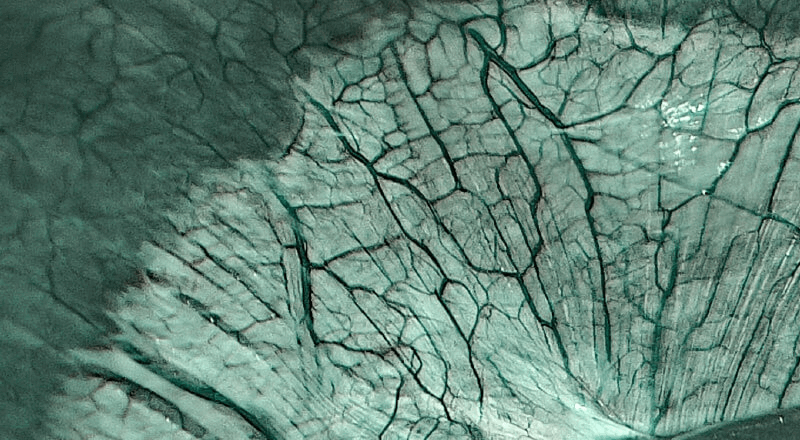

是一种基于血红蛋白对不同波长光吸收系数不同的原理而设计的智能染色成像系统,兼有电子染色和光学染色功能,能够凸显粘膜血管结构,有助于病灶部位识别和诊断,为临床医生术中判断提供参考信息。

血管对比度分布光谱曲线

VIST光谱

光电复合染色成像